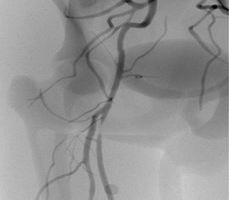

股淺動脈介入手術(shù)模塊

可練習(xí)股淺動脈支架手術(shù)的完整過程:造影診斷、導(dǎo)絲通過、導(dǎo)引導(dǎo)管的放置、預(yù)擴張、自擴張支架放置、后擴張、以及再造影等